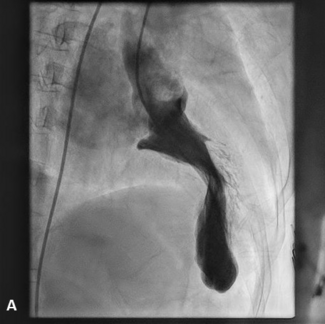

The authors report a case of annulus rupture post-balloon dilation during transcatheter aortic valve replacement , which was sealed successfully with the valve-in-valve implantation technique.